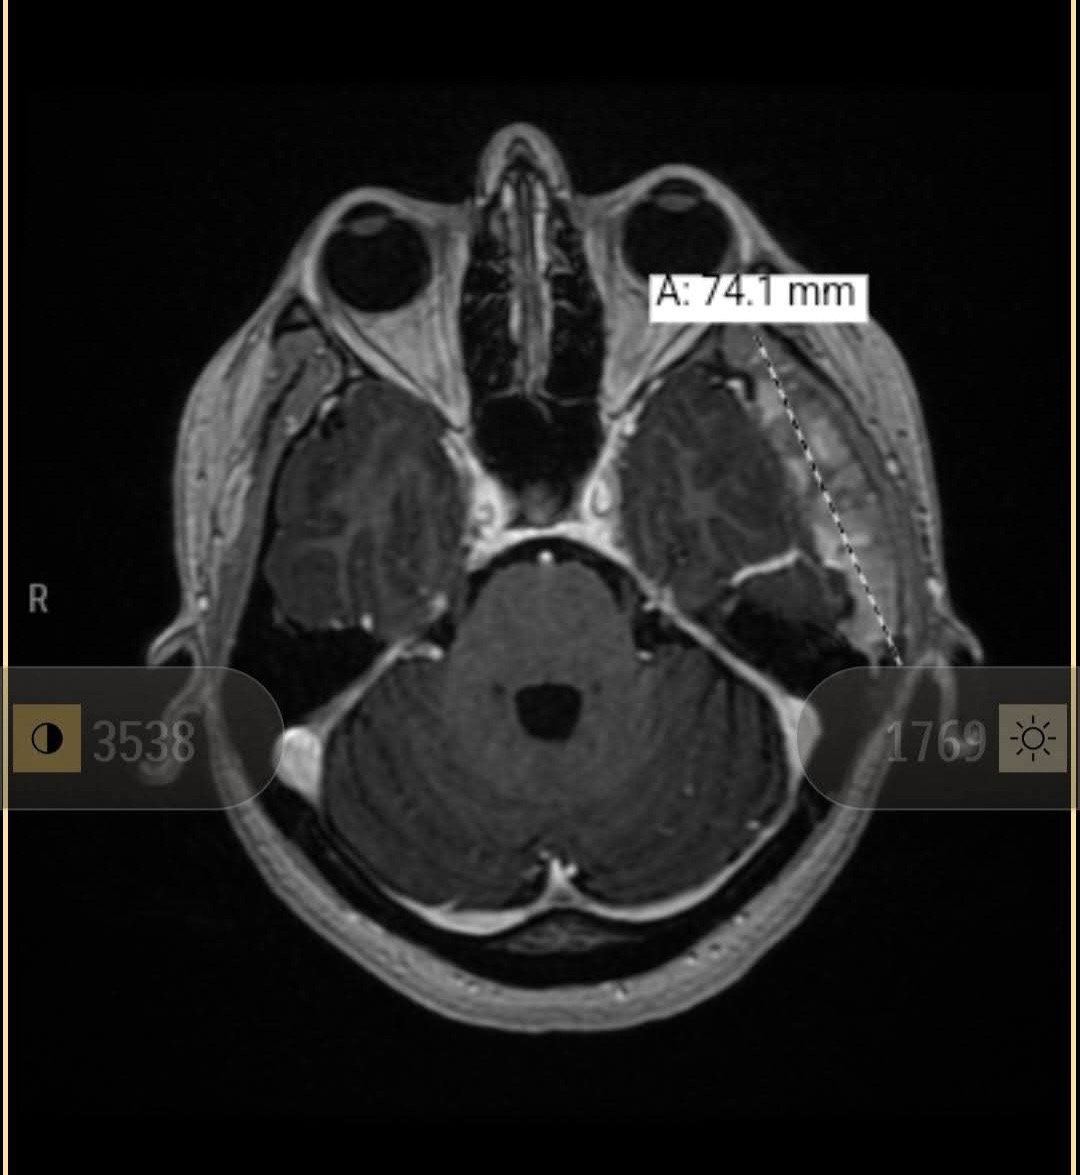

In May 2024, I was sent to see a migraine specialist for my chronic migraines I have suffered from for over a decade. He sent me to get an MRI brain scan done, and they found out that I had a relatively big mass under my skull, right next to my brain. He referred me to a neurologist to get more testing done and hopefully figure out what this could be and if it was causing any of my chronic migraines or other conditions, such as migraines with auras (intense rainbow worms or zig-zagging rainbow lines in my vision at random times). I had asked my optical doctor about these symptoms at the beginning of 2024 at an eye exam, and she had said it was neurological, nothing to do with my vision itself.

I started seeing a neurologist who ordered lots of tests, such as C/T head scans, nuclear bone scans, MRIs with and without contrast, bloodwork, and other tests to try determining what it could be/rule out the possibility of a cyst or cancer. However, none of these tests can give you a true diagnosis, so that is why I was sent to a neurosurgeon to perform a brain biopsy. During this procedure, they put you to sleep and clamp your head into place in order to cut open your scalp, drill a small burr hole, and remove a few small samples to send out to different places for testing. They also did a FISH test to rule out some genetic abnormalities such as some cancer cells, which did come back negative (yay!).

Apparently, I had gotten an MRI done at the age of 18 at Dayton Children's, which neither my parents nor I remember, and there is no information available about what doctor did the testing a decade ago. They were able to pull up the image from this MRI and see that the mass was there 10yrs ago but has grown in size since.

My neurologist team believes it is fibrous dysplasia (extra bone growth of the skull) based on the tests that have come back, and hope to treat it with medication and other methods to decrease the size before considering a full removal, which would require a major reconstructive surgery of my skull. If they did have to remove the mass, a large chunk of skull that has been bulged out from it growing would have to be removed and replaced with a custom 3D printed plate to cover my brain.